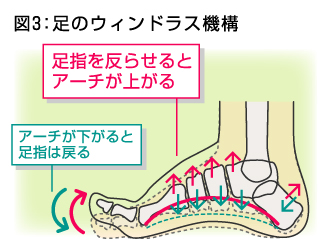

- 足底腱膜=ウィンドラス機構と時に活躍します

- ウィンドラス機構=歩行時に足趾の中足趾節関節の背屈時に、腱膜が巻き上げられることをいいます。この時に内側縦アーチは高くなります。